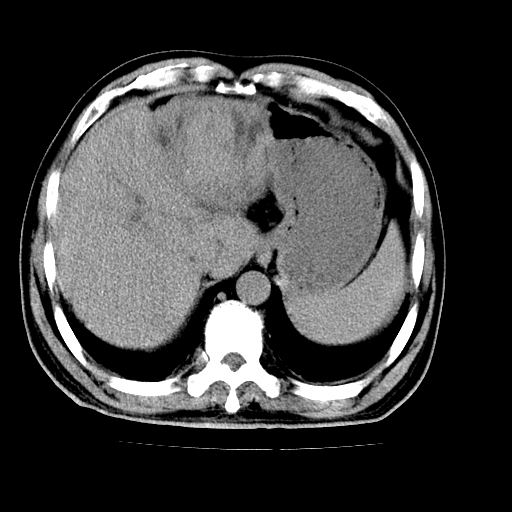

男,66岁,上腹部不适、黄染一周。彩超示:肝左叶占位,肝内胆管扩张,胆总管扩张,胆总管占位?

肝左叶不规则软组织肿块影,边缘不规整邻近肝实质受累分界不清;肝内胆管(左叶)明显扩张成“软藤状”,诊断:肝左叶胆管细胞癌。

肝左叶占位性病变,并胆管扩张,符合胆管细胞癌ct表现,门脉左支受累,左肾囊肿。窗宽太窄了,其他的看不清

左叶胆管细胞癌累及胆总管,门脉左支受侵,慢性胆囊炎胆结石,左肾小囊肿